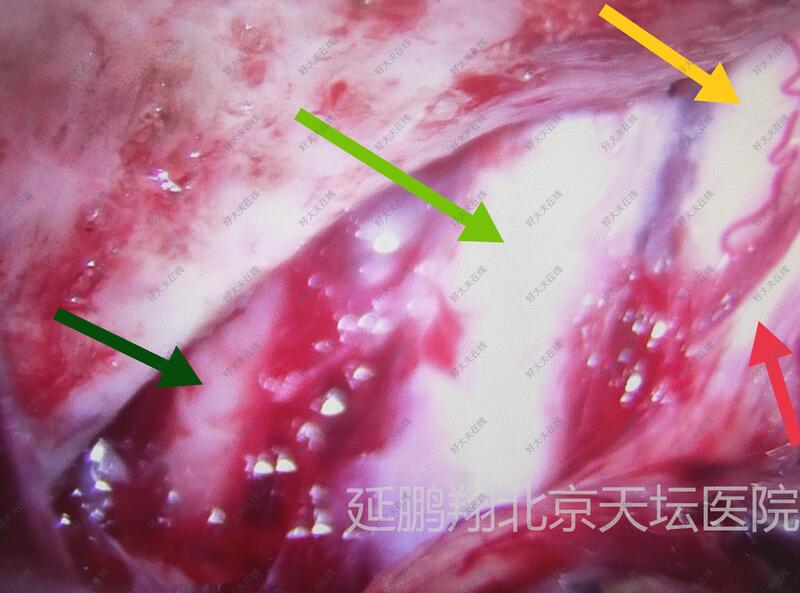

手术在全麻下进行,釆用左额颞入路,先切断肿瘤基底,阻断血供。肿瘤质地软,与脑组织粘连不紧,易分离,两者相隔有蛛网膜(图2),肿瘤切除后左侧嗅神经,视神经,颈内动脉,动眼神经均保护完好(图3)。